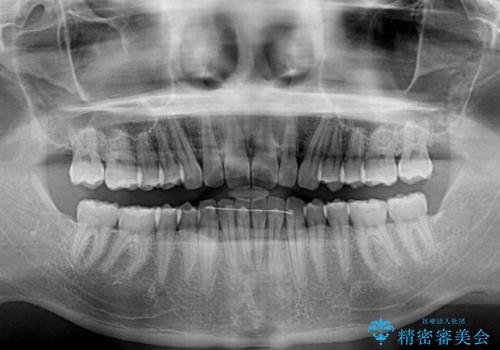

デコボコがなくなったことで日頃の清掃が行いやすくなり、深い咬み合わせが改善したことで、食いしばりによる顎の負担も軽減されました。